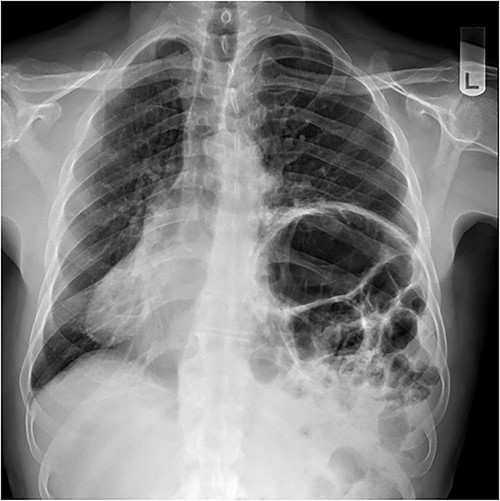

A 79-year-old male was referred by his general practitioner for consideration for repair of diaphragm eventration. The elevated left hemidiaphragm was noted on chest X-ray approximately a decade before. Referral was prompted by an episode of postprandial shortness of breath and a long-standing inability to belch. Medical history is significant for hypertension and tachyarrhythmia controlled on Flecainide. Clinical examination was remarkable for the presence of bowel sounds in the left chest at the level of the nipple, and apex beat on the right. Chest X-ray showed a markedly elevated left hemidiaphragm with dextrocardia (Fig. 1). Pulmonary function tests (PFT) showed small airway defect with normal lung volumes and diffusion capacity. Chest computed tomography showed no pathology other than the eventration.